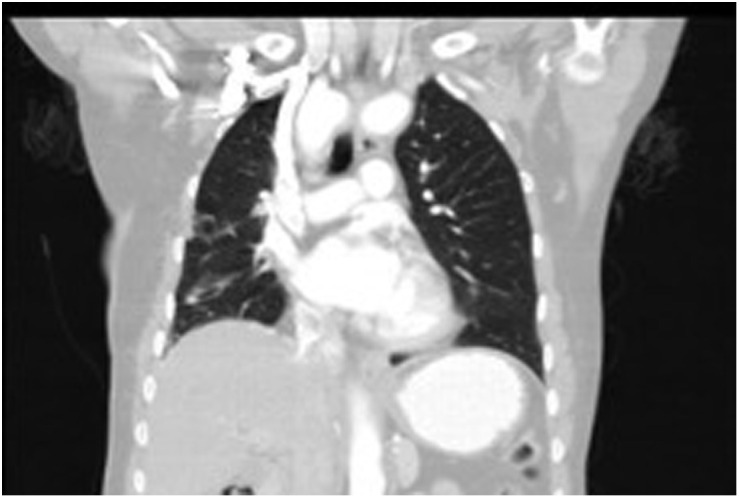

A preoperative CT of the chest revealed 3 lesions in the right lung and a mass on the diaphragm between the right lung’s lower lobe and the heart (Figure 1A-E). Dimensions of the mass were 6 × 8 × 6 cm. Two of the lesions were in the middle lobe, and the third was in the upper lobe. The biggest one (3.6 × 3.2 × 3.6 cm) was in the middle lobe associated with surrounding atelectasis, and the lesion was lying on the parietal pleura. The inner part of the lesion had a low density. The preliminary diagnosis indicated an abscess or infected hydatid cysts. Within the same lobe, a lateral lesion, 1.4 × 1.3 cm, was observed with the same density and radiologic diagnosis. The upper lobe lesion, 2.4 × 1.3 cm, involved a minor fissure lying on the parietal pleura and had a soft tissue density. Multiple calcific and non-calcific lymph nodes were also followed in the mediastinal area. The suspected radiologic diagnosis was an infectious process. Common carotid arteries were separately arising from ascending aorta. Truncus brachiocephalicus was absent. Aorta was at the right paravertebral region. As the 2 pleural biopsies in chest disease show benign cytology and suspected infection process radiologically, genetic study (including BRAF mutation) has not been done. Since the periferal location, the bronchoscopic examination has not been performed.

Figure 1.

(A) Two middle lob lesions. (B) Mass on the diaphragm between right lower lobe and heart. (C) Axial CT image showing middle lobe tumors. (D) Axial CT image showing middle and upper lobe tumors. (E) Axial CT image showing the mass on the diaphragm anteriorly. CT, computed tomography.